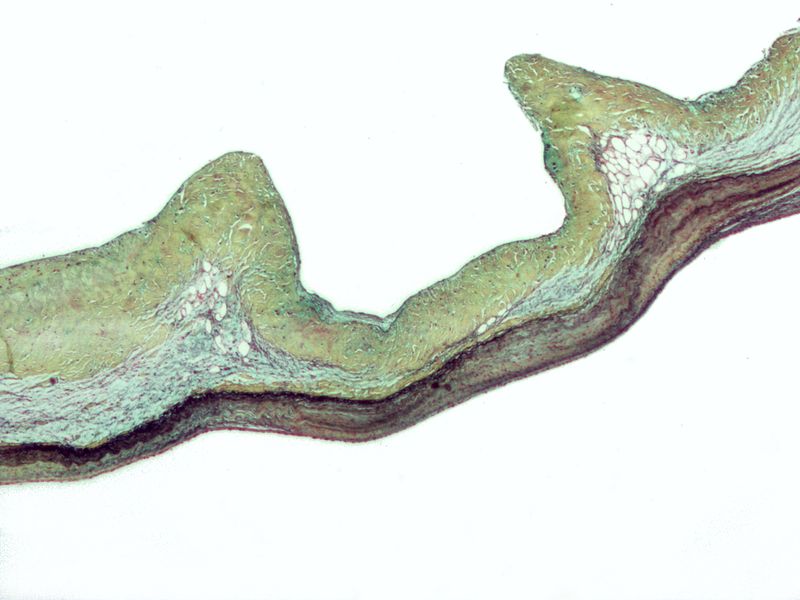

Histology classically shows reactive histiocytes with slender, wavy nuclei are known as Anitschkow cells, Aschoff bodies, gigantic cells, and fibrinoid material.

Chronic rheumatic heart disease develops when rheumatic fever-related valve scarring leads to stenosis with the classic fish-mouth appearance.

In chronic rheumatic heart disease, the chordae tendineae and cusps thicken as a result of the mitral valve being involved almost always.

Quite often the aortic valve is involved, which results in the commissures fusing together.